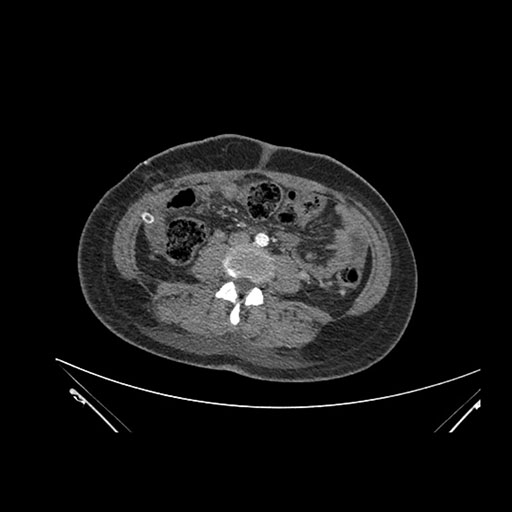

Imaging Analysis

Look through the patient's CT scan to identify any areas of concern for the necessary procedure.

Coronal Arterial

Based on initial findings, which issue(s) would you be most concerned about?